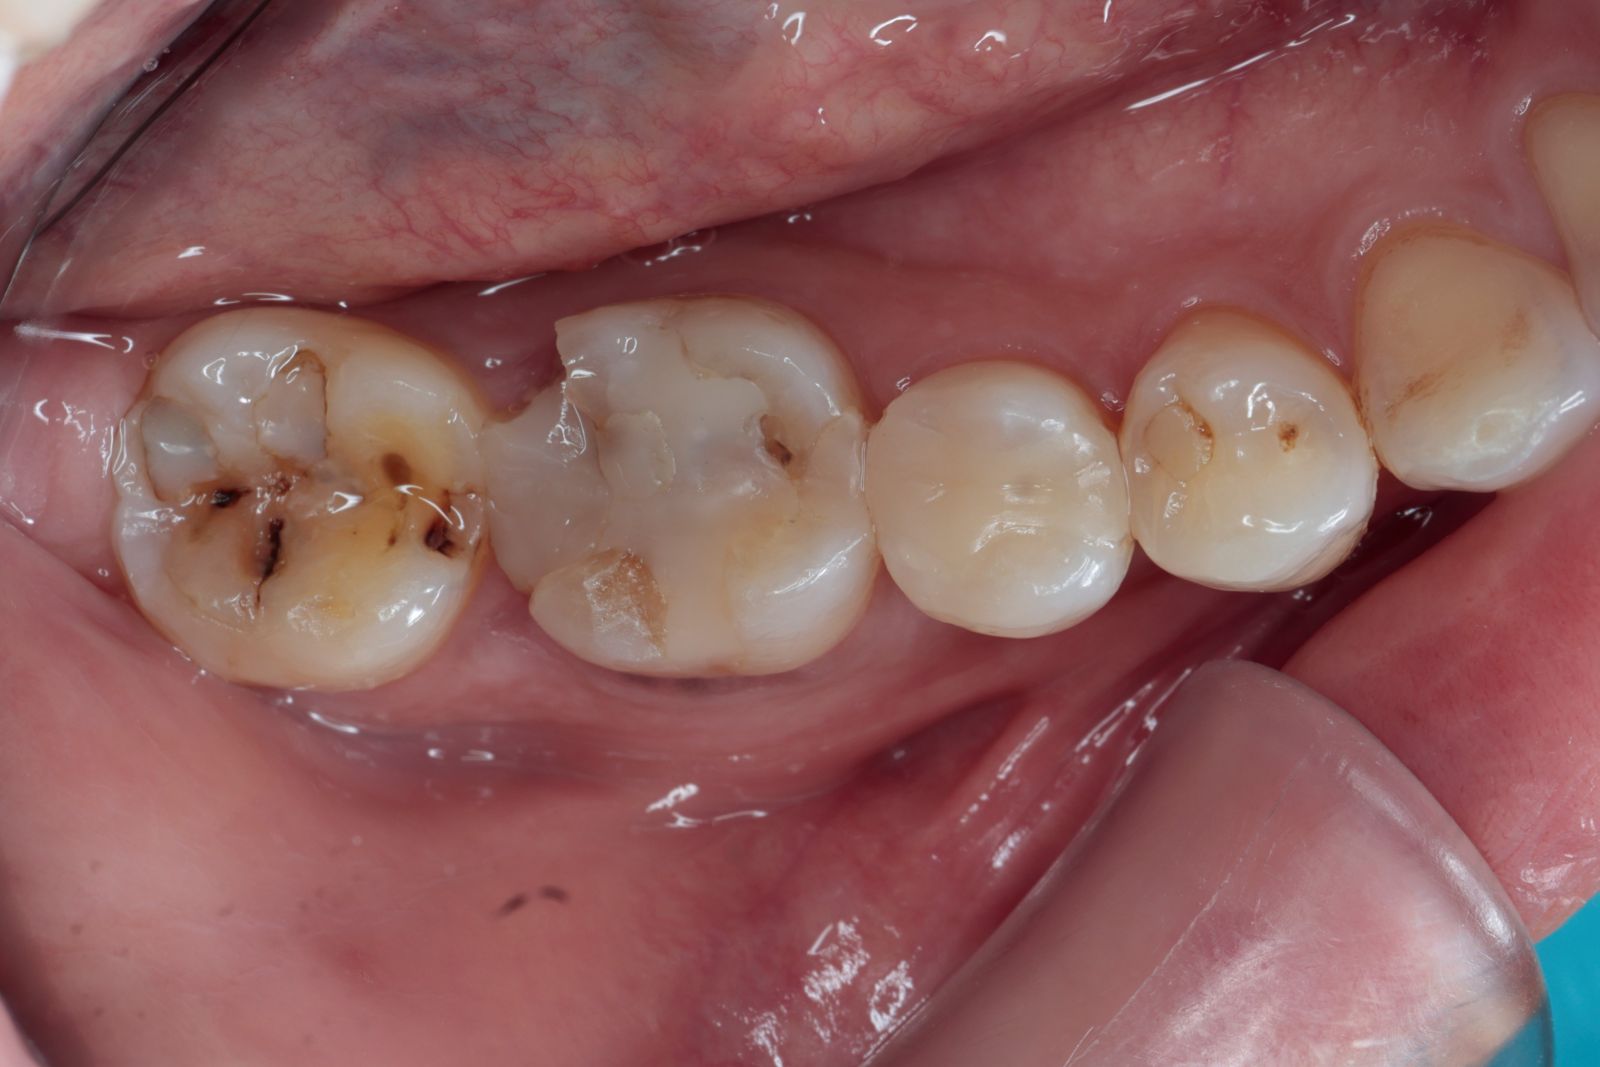

【 案 例 四】